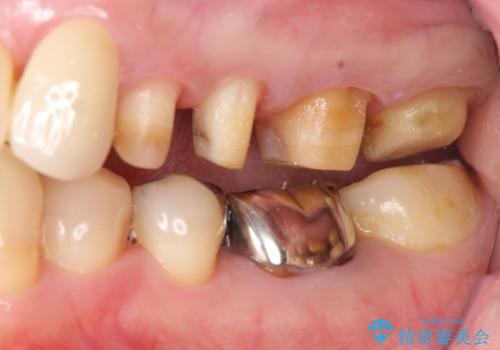

奥歯の被せ物のやり直し 精密根管治療

- 左上の一番奥の歯の根の治療を行いつつ、手前の歯の被せ物のやり直しも一緒に行いました。

根の治療は当法人の根管治療の認定医である林先生にお願いしました。